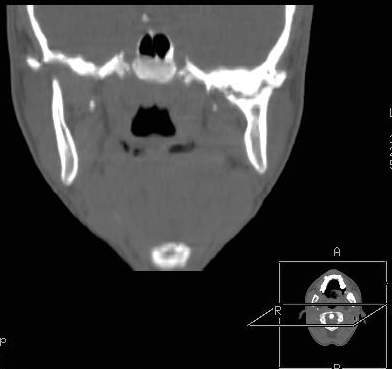

Пациент В., 13 лет. Диагноз: Костный анкилоз левого височно-нижнечелюстного сустава (ВНЧС), левосторонняя микрогения. Болеет с 2-х летнего возраста. Возможная причина развития анкилоза – воспалительный процесс (в первые 1,5 года жизни часто болел простудными заболеваниями, травму родители отрицают). В 3 и 5 лет проводилась редрессация – безуспешно. Прилагаются: ортопантомограмма, кадры СКТ с 3Д реконструкцией. Вопросы: определение тактики лечения – вид и сроки реконструктивно-пластической операции (этапов операции), а именно – неоартропластики и устранения микрогении, медикаментозная терапия в до- и послеоперационный период, ортодонтическое лечение.